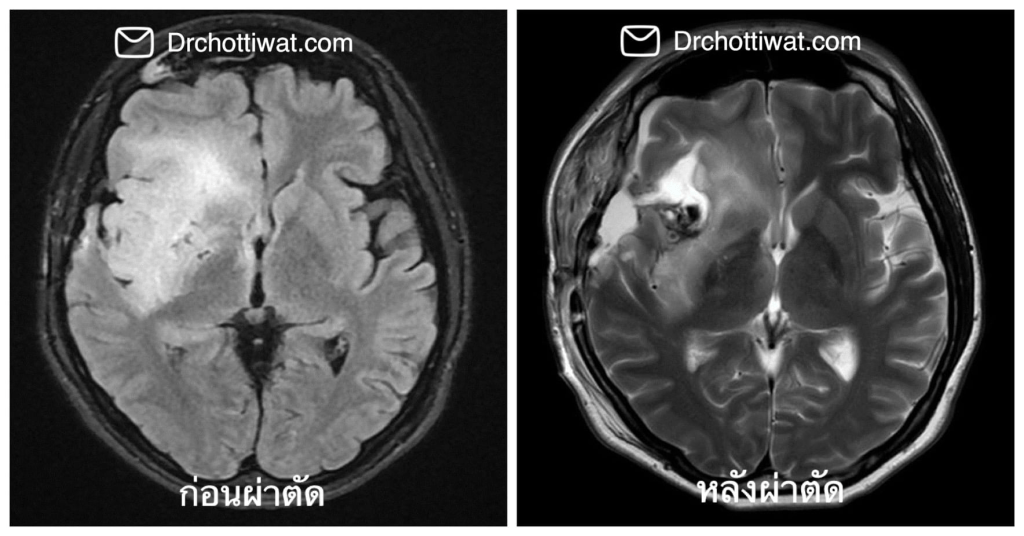

ผู้ป่วยรายหนึ่งมาพบหมอเนื่องจากตรวจพบว่ามีเนื้องอกชนิดกลิโอมาที่สมองข้างขวา 2ปีต่อมาก้อนเนื้องอกใหญ่ขึ้นเรื่อยๆจนผู้ป่วยไม่สามารถทำงานได้และตรวจพบความผิดปกติของการทำงานหลายด้าน จากภาพเอกซเรย์ก้อนส่วนใหญ่ของผู้ป่วยรายนี้จัดว่าอยู่ในบริเวณของสมองที่ “ไม่สำคัญ” และประสาทศัลยแพทย์ส่วนใหญ่ก็คงตัดทิ้งโดยไม่ลังเล โดยระวังไม่ให้ผู้ป่วยเป็นอัมพาตเท่านั้น

ด้วยความร่วมมือจากทีมจิตแพทย์ในการตรวจติดตามขณะผ่าตัดและทำผ่าตัดแบบตื่นเพื่อทดสอบการทำงานของสมอง ทำให้เราสามารถเก็บรักษา “อารมณ์” ของผู้ป่วยรายนี้ไว้ได้ ผู้ป่วยสามารถกลับไปช่วยเหลือตนเองได้ และอาการดีขึ้นเรื่อยๆจนสามารถกลับไปจัดรายการวิทยุและรับงาน MC ได้ตามปกติแล้ว